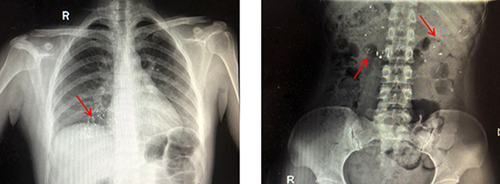

醫(yī)生解釋,水銀體溫計是由玻璃和金屬汞構(gòu)成,咬碎后的碎片可能會導(dǎo)致口腔、咽喉部、胃腸道黏膜的損傷,嚴(yán)重者甚至?xí)?dǎo)致穿孔。水銀經(jīng)胃腸道吸收甚微,但誤吞水銀者如果胃腸道黏膜有潰瘍傷口,水銀便會經(jīng)潰瘍或者傷口立刻進入人體血液,這樣吸收的汞會產(chǎn)生較大的毒性,嚴(yán)重可危及生命安全。而及時攝入蛋清、牛奶等可有效保護消化道黏膜,減少毒物的吸收。后經(jīng)急診科醫(yī)護人員進行專業(yè)的清理口腔,洗胃,催吐,加速排泄等措施,終于將孩子腸胃內(nèi)殘留的水銀排泄干凈。

首先,讓孩子立即離開打碎水銀的房間,仔細(xì)觀察孩子口腔是否有劃傷,取出孩子口中的玻璃碎片。接下來,看孩子的手指是否被劃傷,清理孩子接觸汞的部位。對于吞服了水銀的寶寶,可以先讓他喝一些蛋清、牛奶或豆?jié){保護胃腸黏膜;最后,盡快帶孩子去醫(yī)院就診。處理完孩子這邊,就是對于環(huán)境的處理了。暴露在空氣中的水銀很容易揮發(fā)到空氣,但這比誤吞入肚的水銀更危險。因為水銀在空氣中揮發(fā)后,會變成汞蒸氣,它很容易被吸入體內(nèi),從而引起中毒。由于水銀在高溫下更容易揮發(fā),所以要立即關(guān)閉暖氣。關(guān)閉所有通向其他房間的門窗,打開被污染的房間的門窗,保持至少24小時的通風(fēng)。用小鏟子或戴上手套用濕潤的小棉棒或膠帶紙將灑落在地面上的水銀粘集起來并放入密封小瓶中;然后在瓶中加入少量水,并在瓶上寫明“廢棄水銀”等辨識性文字后,丟至合適的垃圾桶里。